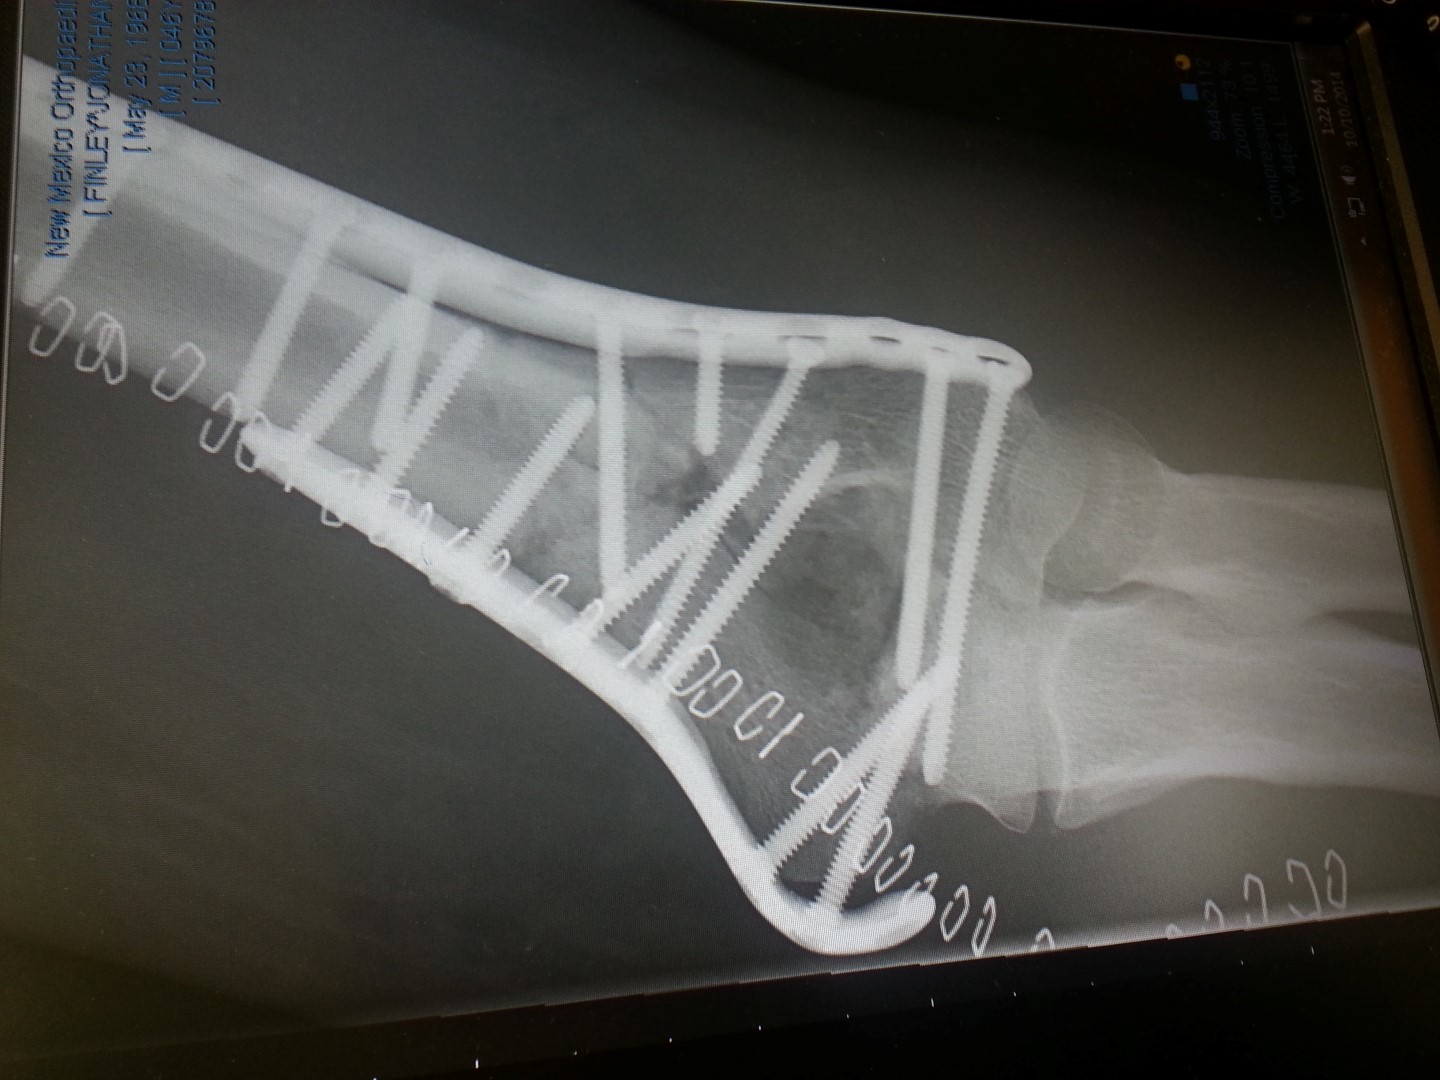

After getting the bone healed, ligament damage was found that needed repaired. So, two “collateral ligament reconstruction” surgeries followed.

I cannot begin to express the disbelief that fills me about this whole situation. Previously, I would never have thought that an accident on a bicycle could change a person’s life so dramatically. I have had four surgeries over the last two years and have been in a cast/splint/brace for almost one whole year. When not in a cast/splint/brace, the use of my arm has been very limited. Of course, being unable to use one arm puts a great deal of stress on the other arm. I have ended up hurting my right shoulder twice as a result. Even today, two years later, I have very little arm strength – especially the tricep muscle (that was cut in half during the first surgery) and with the last ligament reconstruction being on June 15 (three and a half months ago), I have to be very careful with it.